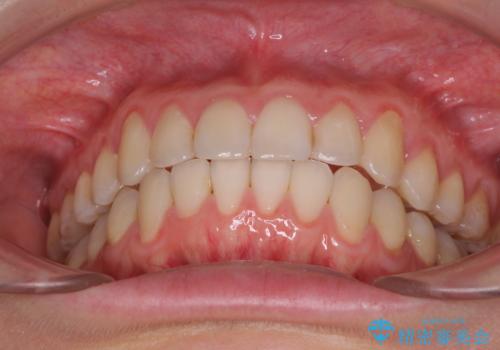

1日22時間の装着時間をしっかり守ってくださったので、予定していた1年よりも早く治療を終えることができました。

インビザライン矯正特有の奥歯がしっかりと咬合しない感覚も改善され、大変満足していただきました。